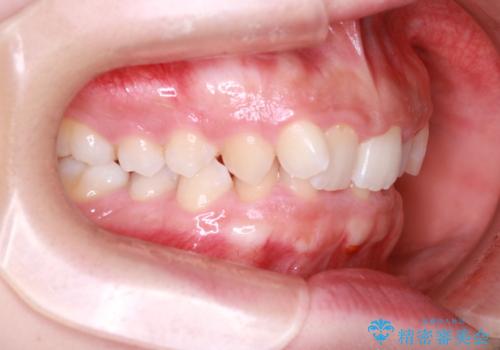

インビザラインで整える深い噛み合わせ

- 患者様は、ディープバイト(深い噛み合わせ)と、咬合平面の左下がりが気になるとのことでご来院されました。診断の結果、非抜歯で治療可能と判断し、透明なマウスピース型矯正装置「インビザライン」を用いる方針としました。治療では、歯列全体の調整を行いながら、咬合平面の水平化を重点的に進める計画を立案しました。2年間で計画的にマウスピースを交換し、左右のバランスと噛み合わせの改善を目指しました。

ディープバイトの矯正は、噛み合わせが深くなりがちなため、細心の注意を払いながら進める必要があります。本症例では、奥歯の高さを調整しつつ前歯の噛み合わせを浅くすることで、全体の咬合バランスを整えました。また、咬合平面の左下がりを修正する過程で、歯列に不均等な力がかからないよう、インビザラインのアタッチメント配置を最適化しました。患者様には装着時間を守っていただき、治療が計画通り進むよう協力をお願いしました。治療終了後には、リテーナーを装着して安定性を確保しました。